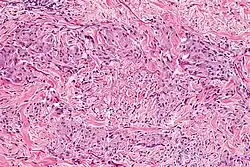

Granuloma annulare microscopically consists of dermal epithelioid histiocytes around a central zone of mucin—a so-called palisaded granuloma.[4]